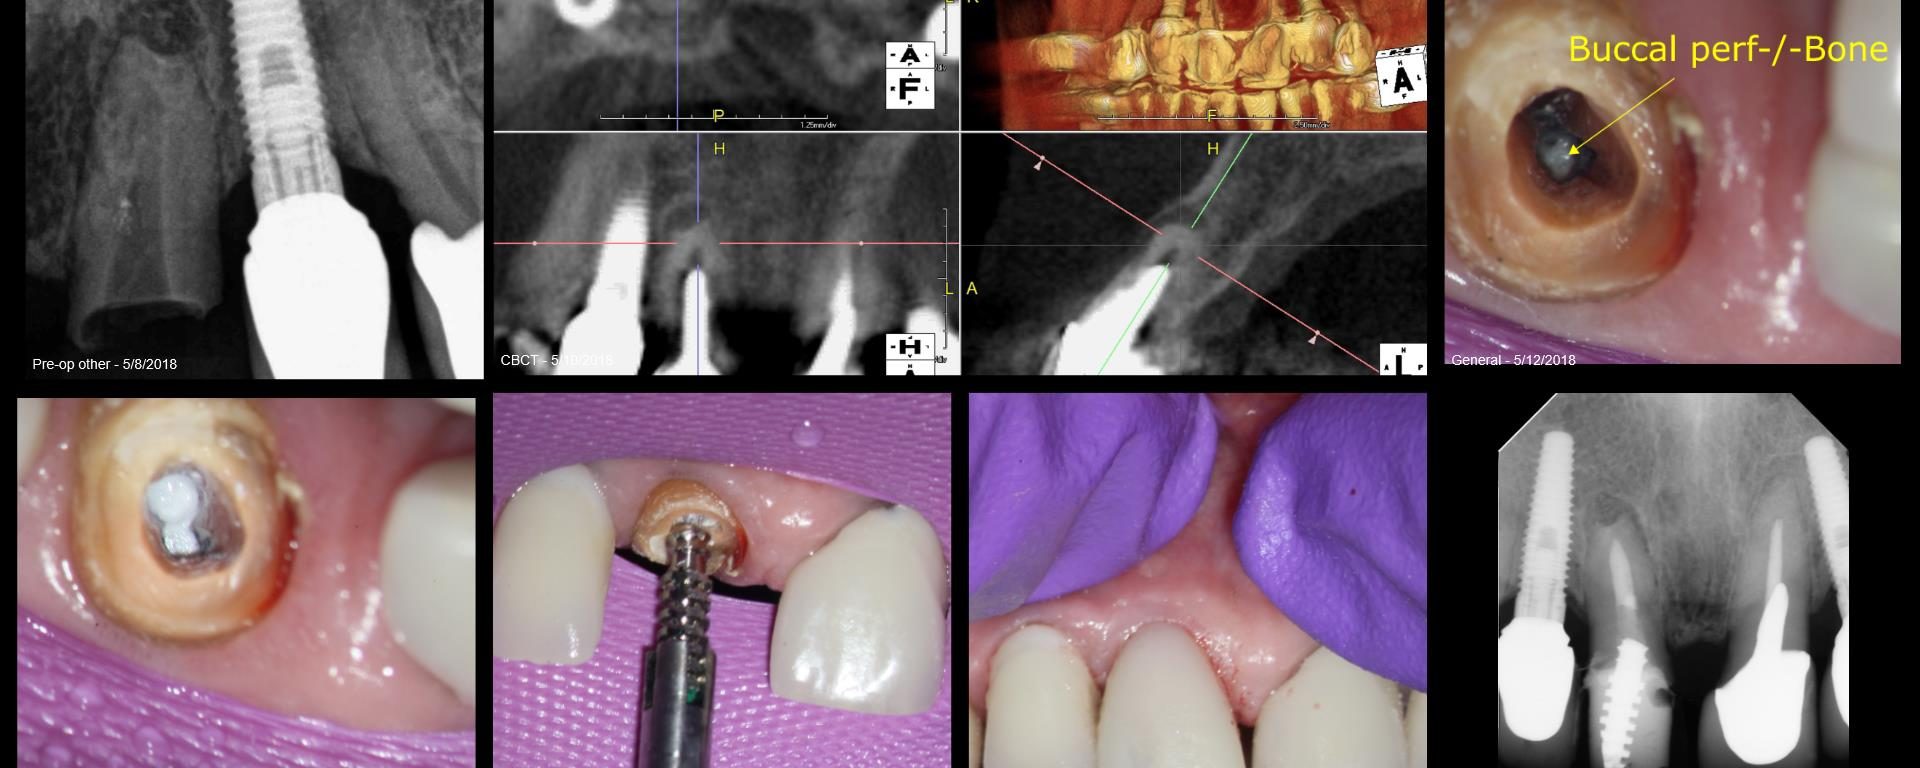

Because this was a Zirconia crown, my approach was to make a “staging platform” where I thought the access points would be. Proabbaly made the platform larger than I needed to. In this case, the X-nav was spot-on. I’m nowhere near Charles or Pushpak, but I am getting more comfortable with it. This took longer […]